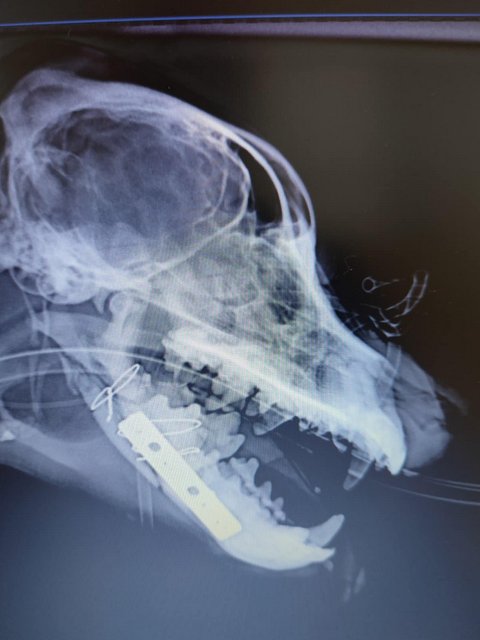

Röntgenbilder zeigten das Ausmaß der Zerstörung des Unterkiefers und den Bruch eines Beines.

Dieser Hund muss grausame Schmerzen haben, Zähne sind aus der Verankerung gerissen und sein Gesichtsschädel ist nicht mehr symmetrisch. Ein großes Stück des Unterkiefers ist komplett abgebrochen.

Es braucht sicher viel Geschick, um das wieder so zusammenzusetzen, dass der Hund später problemlos fressen kann.

Camush Kopf ist wieder symmetrisch, der Kiefer wird jetzt mit Platte und Verdrahtung zusammengehalten und ein paar Zähne fehlen jetzt.